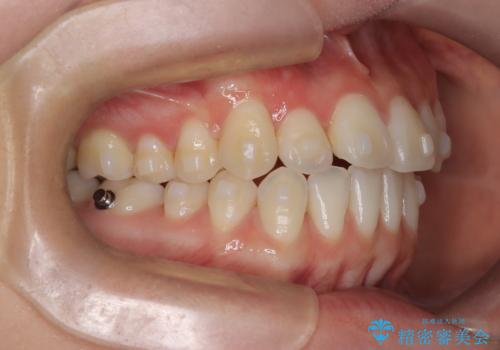

- 八重歯と、右上前歯(2番)が下の歯より内側に入っている反対咬合を気にされてご来院されました。精密な検査の結果、八重歯と反対咬合を同時に改善するためには、歯列全体にスペースを確保する必要があると判明。患者様のご希望から、透明で目立たないインビザライン(マウスピース矯正)による治療計画を立案しました。奥歯全体を奥へ動かす遠心移動でスペースを作り、これらの複雑な問題を一括で解消することを目指します。

今回の矯正治療では、透明なマウスピース型の装置インビザラインを使用しました。治療は、緻密なデジタル計画に基づき、奥歯から順に歯列全体を後方へ移動させる遠心移動を実施。これにより、八重歯を正しい位置に並べるためのスペースを確保しました。同時に、右上の2番を前方に誘導することで反対咬合を解消。結果として、抜歯することなく八重歯と反対咬合という複数の問題が改善され、機能的で美しい歯並びを獲得していただけました。